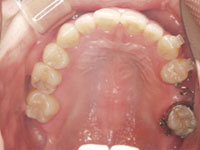

口内写真

口内写真とパノラマレントゲンを撮影し、まずは顎の骨の状態まで詳しく確認しました。.

・歯がない期間が長く続いたため隣の歯が横に倒れてしまい、歯と歯との間に隙間が2ケ所できてしまっていた。

歯がない期間が長く続いたため隣の歯が横に倒れてしまい、歯と歯との間に隙間が2ケ所できてしまっていたため、インプラントの前に矯正治療で隙間をなくす治療を行う